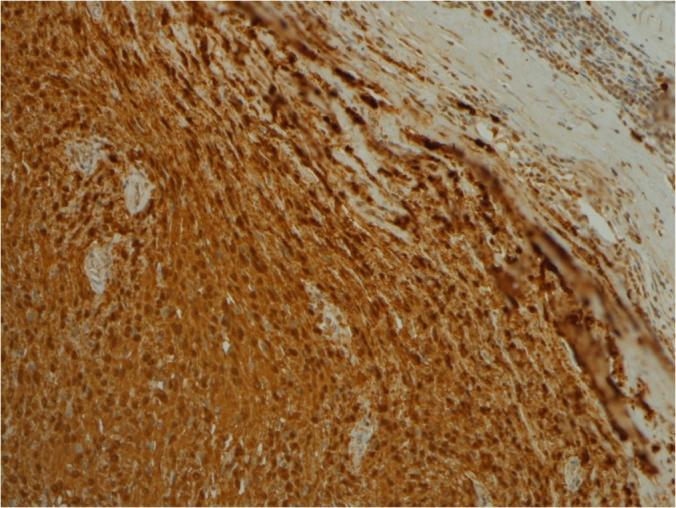

伪装成肾上腺皮质肿瘤的神经鞘瘤:一例报告并文献复习

Schwannoma masquerading as adrenocortical tumor: A case report and review of literature.

Schwannomas arises from retroperitoneal space are rare tumors. Adrenal Schwannomas are often misdiagnosed due to deficient of distinctive radiological findings. We report a case of adrenal schwannoma presented with vague abdominal pain. Initially, the patient was diagnosed as adrenocortical tumor that was treated with robotic adrenalectomy. Histopathological and immuno-histochemical examination revealed schwannoma. We will report the case and review the literature regarding this rare tumor.

摘要

起源于腹膜后间隙的神经鞘瘤是罕见肿瘤。肾上腺神经鞘瘤常因缺乏独特的影像学表现而被误诊。我们报告一例以腹部隐痛为表现的肾上腺神经鞘瘤病例。最初,该患者被诊断为肾上腺皮质肿瘤并接受了机器人辅助肾上腺切除术。组织病理学和免疫组织化学检查显示为神经鞘瘤。我们将报告该病例并复习有关这种罕见肿瘤的文献。